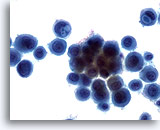

Peritoneal effusion: Metastatic carcinoma of the breast. Many small clusters and single malignant cells contrast with benign mesothelial cells. 20X

Peritoneal effusion:

Metastatic carcinoma of the breast. Many small clusters and single malignant cells contrast with benign mesothelial cells.

20X